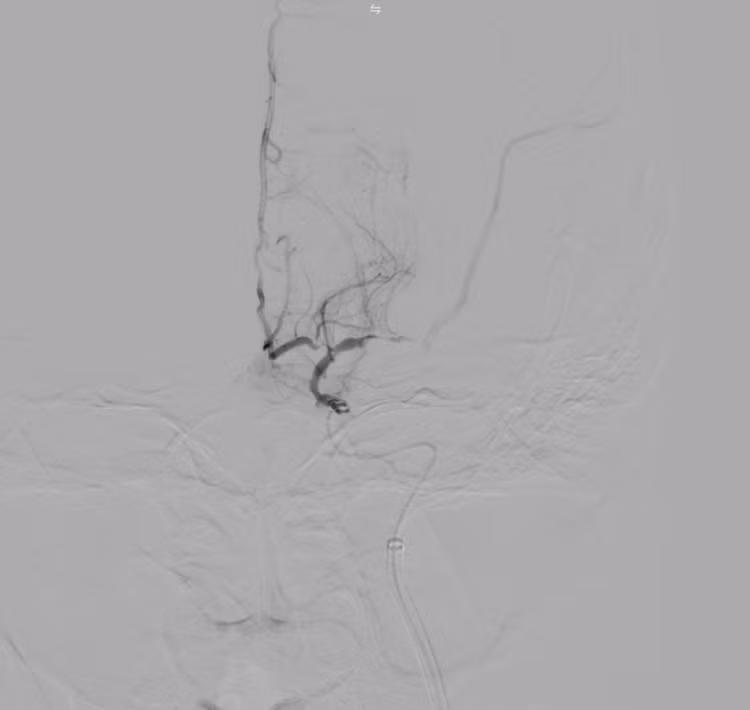

Kết quả chụp DSA xác định tắc động mạch não giữa trái đoạn M1 do hẹp nặng. Kíp can thiệp đã tiến hành nong bóng tái thông mạch máu, khôi phục dòng chảy lên não thành công.

Hình ảnh: DSA trong can thiệp hẹp nặng M1

Hình ảnh: Chụp DSA trước can thiệp thấy tắc M1 trái

Hình ảnh: DSA sau can thiệp tái thông TICI 3